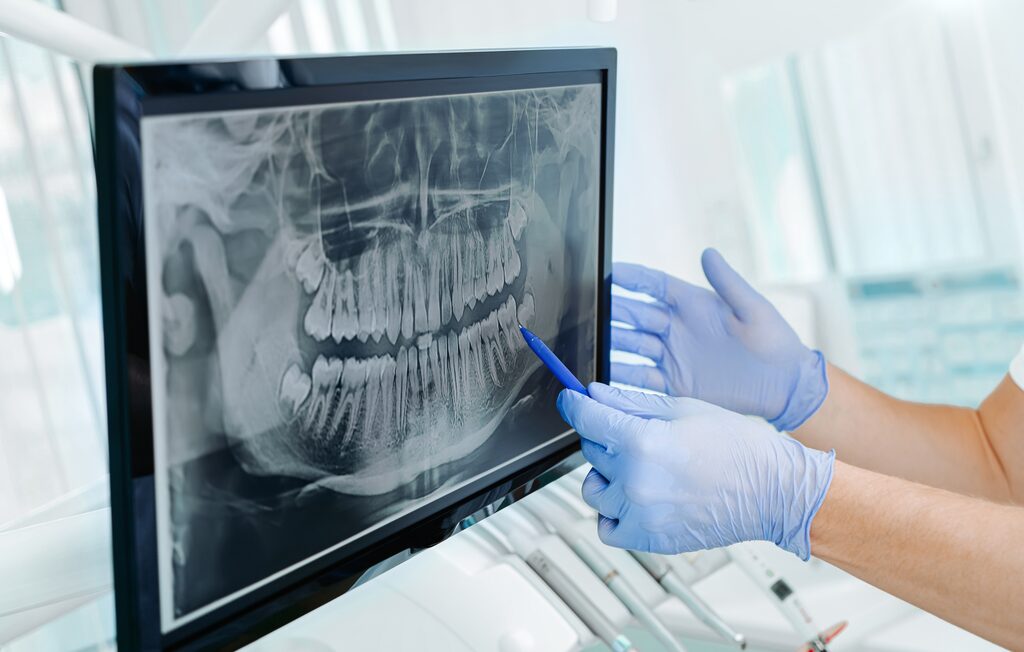

In der modernen Zahnmedizin ist das Röntgen ein elementarer Bestandteil, wenn es darum geht, die Zahngesundheit des Patienten festzustellen. Mit dieser Technik ist es möglich, den Bereich zwischen den Zähnen einzusehen, sowie den Zustand im Inneren eines Zahnes und seine Wurzeln im Kieferknochen zu untersuchen.

Dieses bewährte Verfahren haben wir in unserer Praxis auf den neuesten Stand der Technik gebracht: Bei uns findet nun das digitale Röntgen Anwendung. Die Vorteile für uns als Mediziner, aber auch für Sie als Patienten sind dabei deutlich spürbar: Die Qualität und Handhabung der Aufnahmen ist besser und einfacher. Die Bilder stehen unmittelbar nach der Aufnahme am Computer zur Verfügung. So lassen sich Bereiche gezielt vergrößern und bewerten, der Kontrast ist zu justieren, was eine bessere Bildqualität mit sich bringt und wir so den Beschwerden noch genauer auf den Zahn fühlen können. Vor allem aber wird die Strahlenbelastung, der sie beim Röntgen ausgesetzt sind, mit diesem modernen Verfahren um rund 90% reduziert.